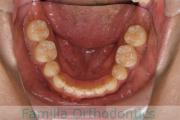

No.22V-398

- 叢生

- 14歳

- 男性

- 抜歯部位

- 上:

- 8448

- 下:

- 主な使用装置:

- FEA 022

- 治療にかかった費用:

- 88万円

八重歯が気になるのを治したいということで来院されました。上下左右から小臼歯を抜歯してマルチブラケット法にて治療を行いました。2年半、30回程度の通院が必要でした。叢生が強く、保定中の後戻りのリスクが高いため、保定がとても重要なケースです。